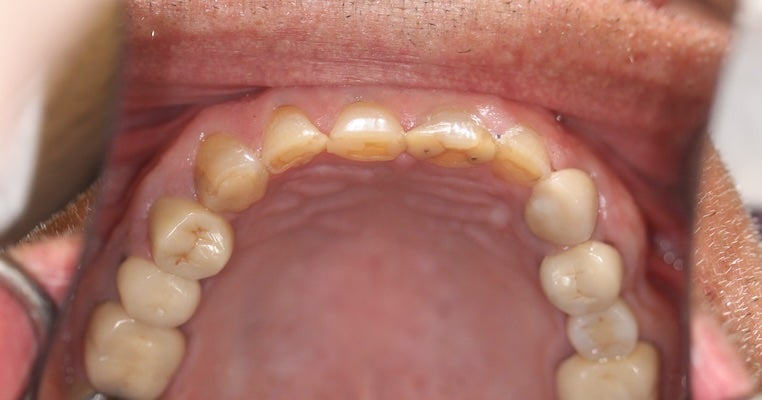

Here we addressed a challenging case of severe tooth decay resulting from chronic, long-term dry mouth. The treatment involved the application of full-mouth porcelain crowns, effectively restoring the patient's oral health and smile.